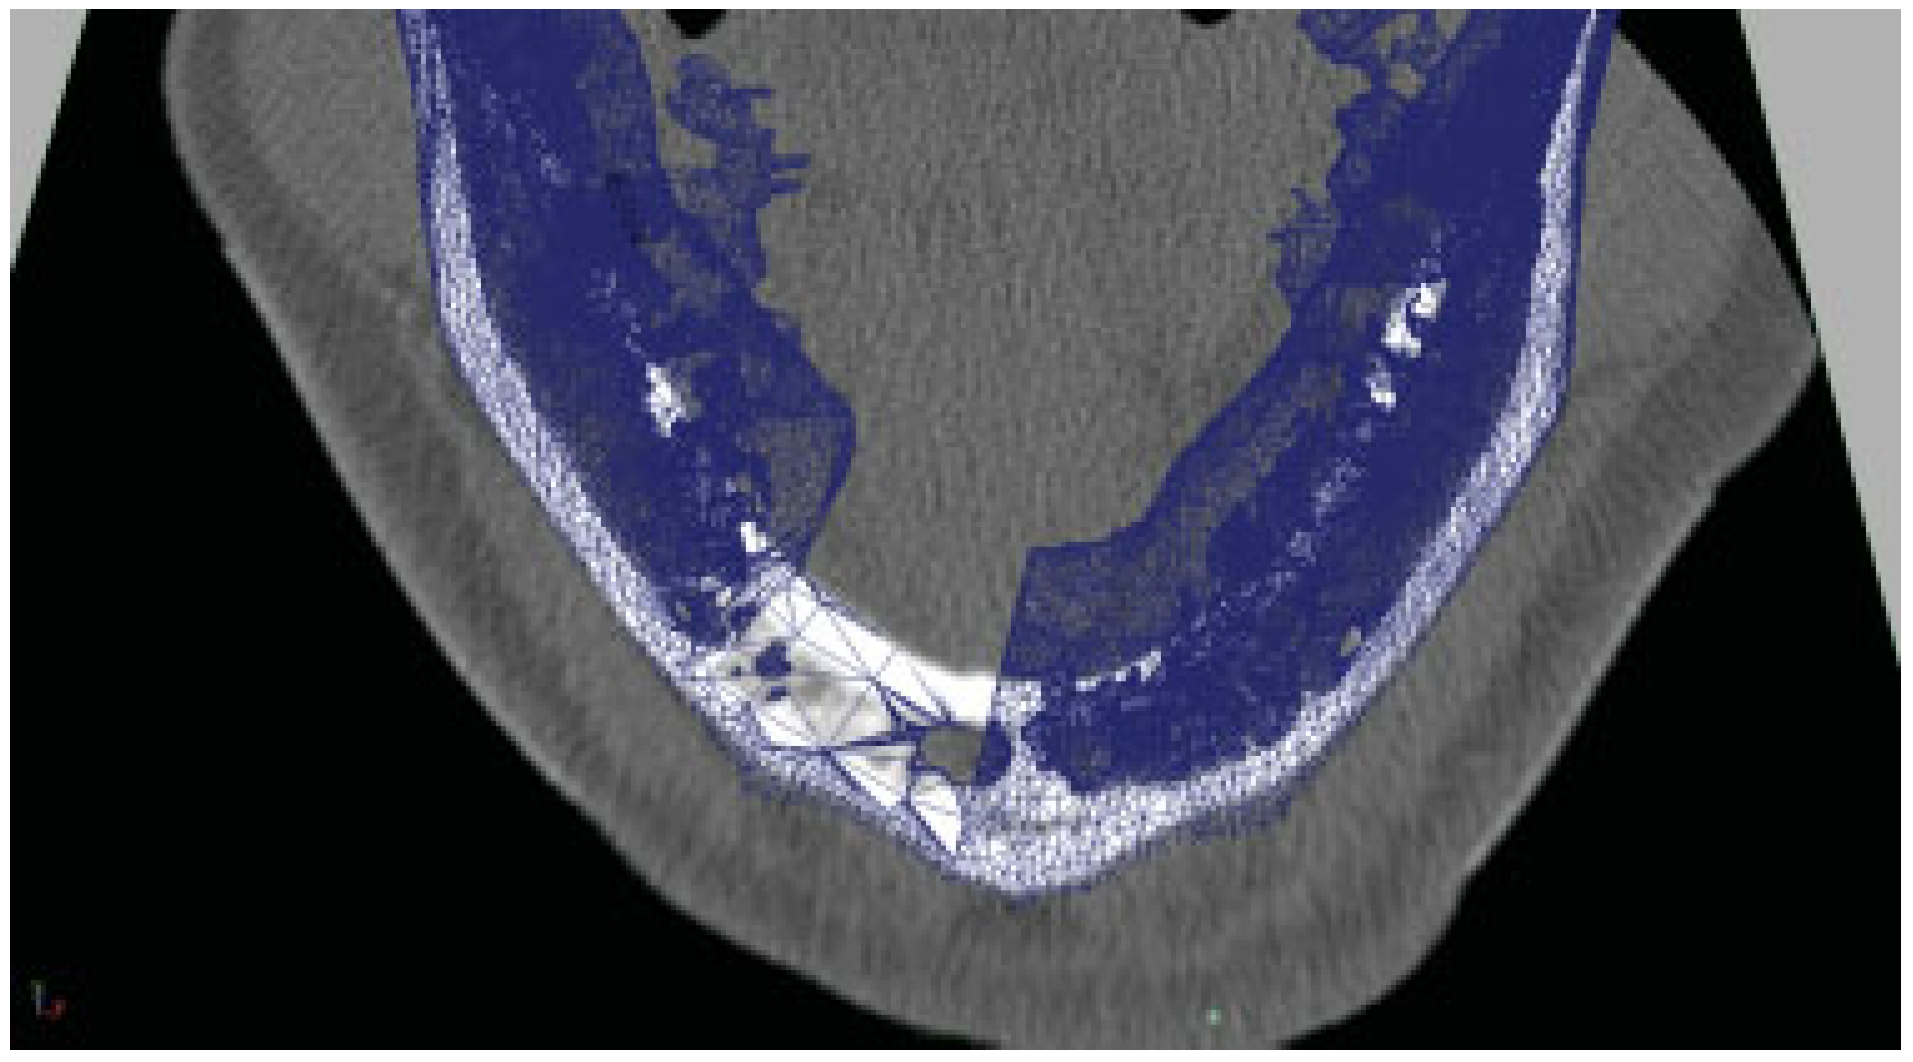

An isosurface reconstruction was carried out in Osirix© 3.2 (Wavefront Technology, Edmonton, Alberta, Canada) using a Hounsfield level of 500. The reconstruction was exported from Osirix© as a geometry definition file, *.obj. The polygon jaw was then transferred to Autodesk Maya 2009 (Autodesk®, San Rafael, CA). The DICOM images stack was exported to *.tiff (Adobe System Inc., San Jose, CA) and imported as an image sequence into Maya® 2009 (Autodesk®, San Rafael, CA). The polygon jaw was then aligned with the image sequence and virtual resection was carried out (Figure 1), and a saw guide was designed (Figure 2A,B). The virtual saw guide was compared to the image sequence for treatment plan accuracy. In the remaining cases, the treatment plan was carried out in Surgicase© (Materialise©, Leuven, Belgium). The *.stl-file (3D System Corp, Rock Hill, SC) from the reconstructed mandible/fibula was transferred to a Macintosh© Mac Book Pro©, 2.16 MHz, Duel Core Intel® processor with two Gigabyte RAM, (Apple© Corp., Cupertino, CA) and imported into 3-D animation program Maya 2009. The specification of a Compact UniLOCK® 2.4 large plate (Synthes®, Switzerland) was used. The geometry was scaled down by 25%. The polygon mesh was skinned onto a skeleton, according to Dérand and Hirsch [5]. Plates were constructed with individualized screw holes (Figure 3) and exported as a geometry definition file, *.obj. The titanium mesh was constructed by mirroring the contralateral side and shaped with Fracture-FX (plug-in, Maya® 2009). All data were transferred over Internet to the Department of Engineering and Sustainable Development (Mid Sweden University, Östersund, Sweden) for additive manufacturing of the devices.

Figure 1. The DICOM files were converted to *.tiff and then imported into Autodesk Maya 2009 (Autodesk). The image was aligned with the polygon mandible to check the resection.